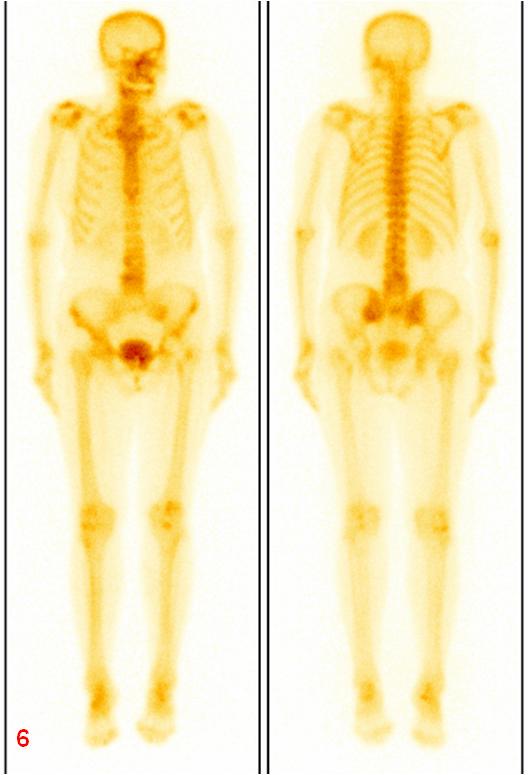

圖6復(fù)查ECT雙側(cè)骶髂關(guān)節(jié)、骶骨及左側(cè)恥骨代謝較前明顯減低。